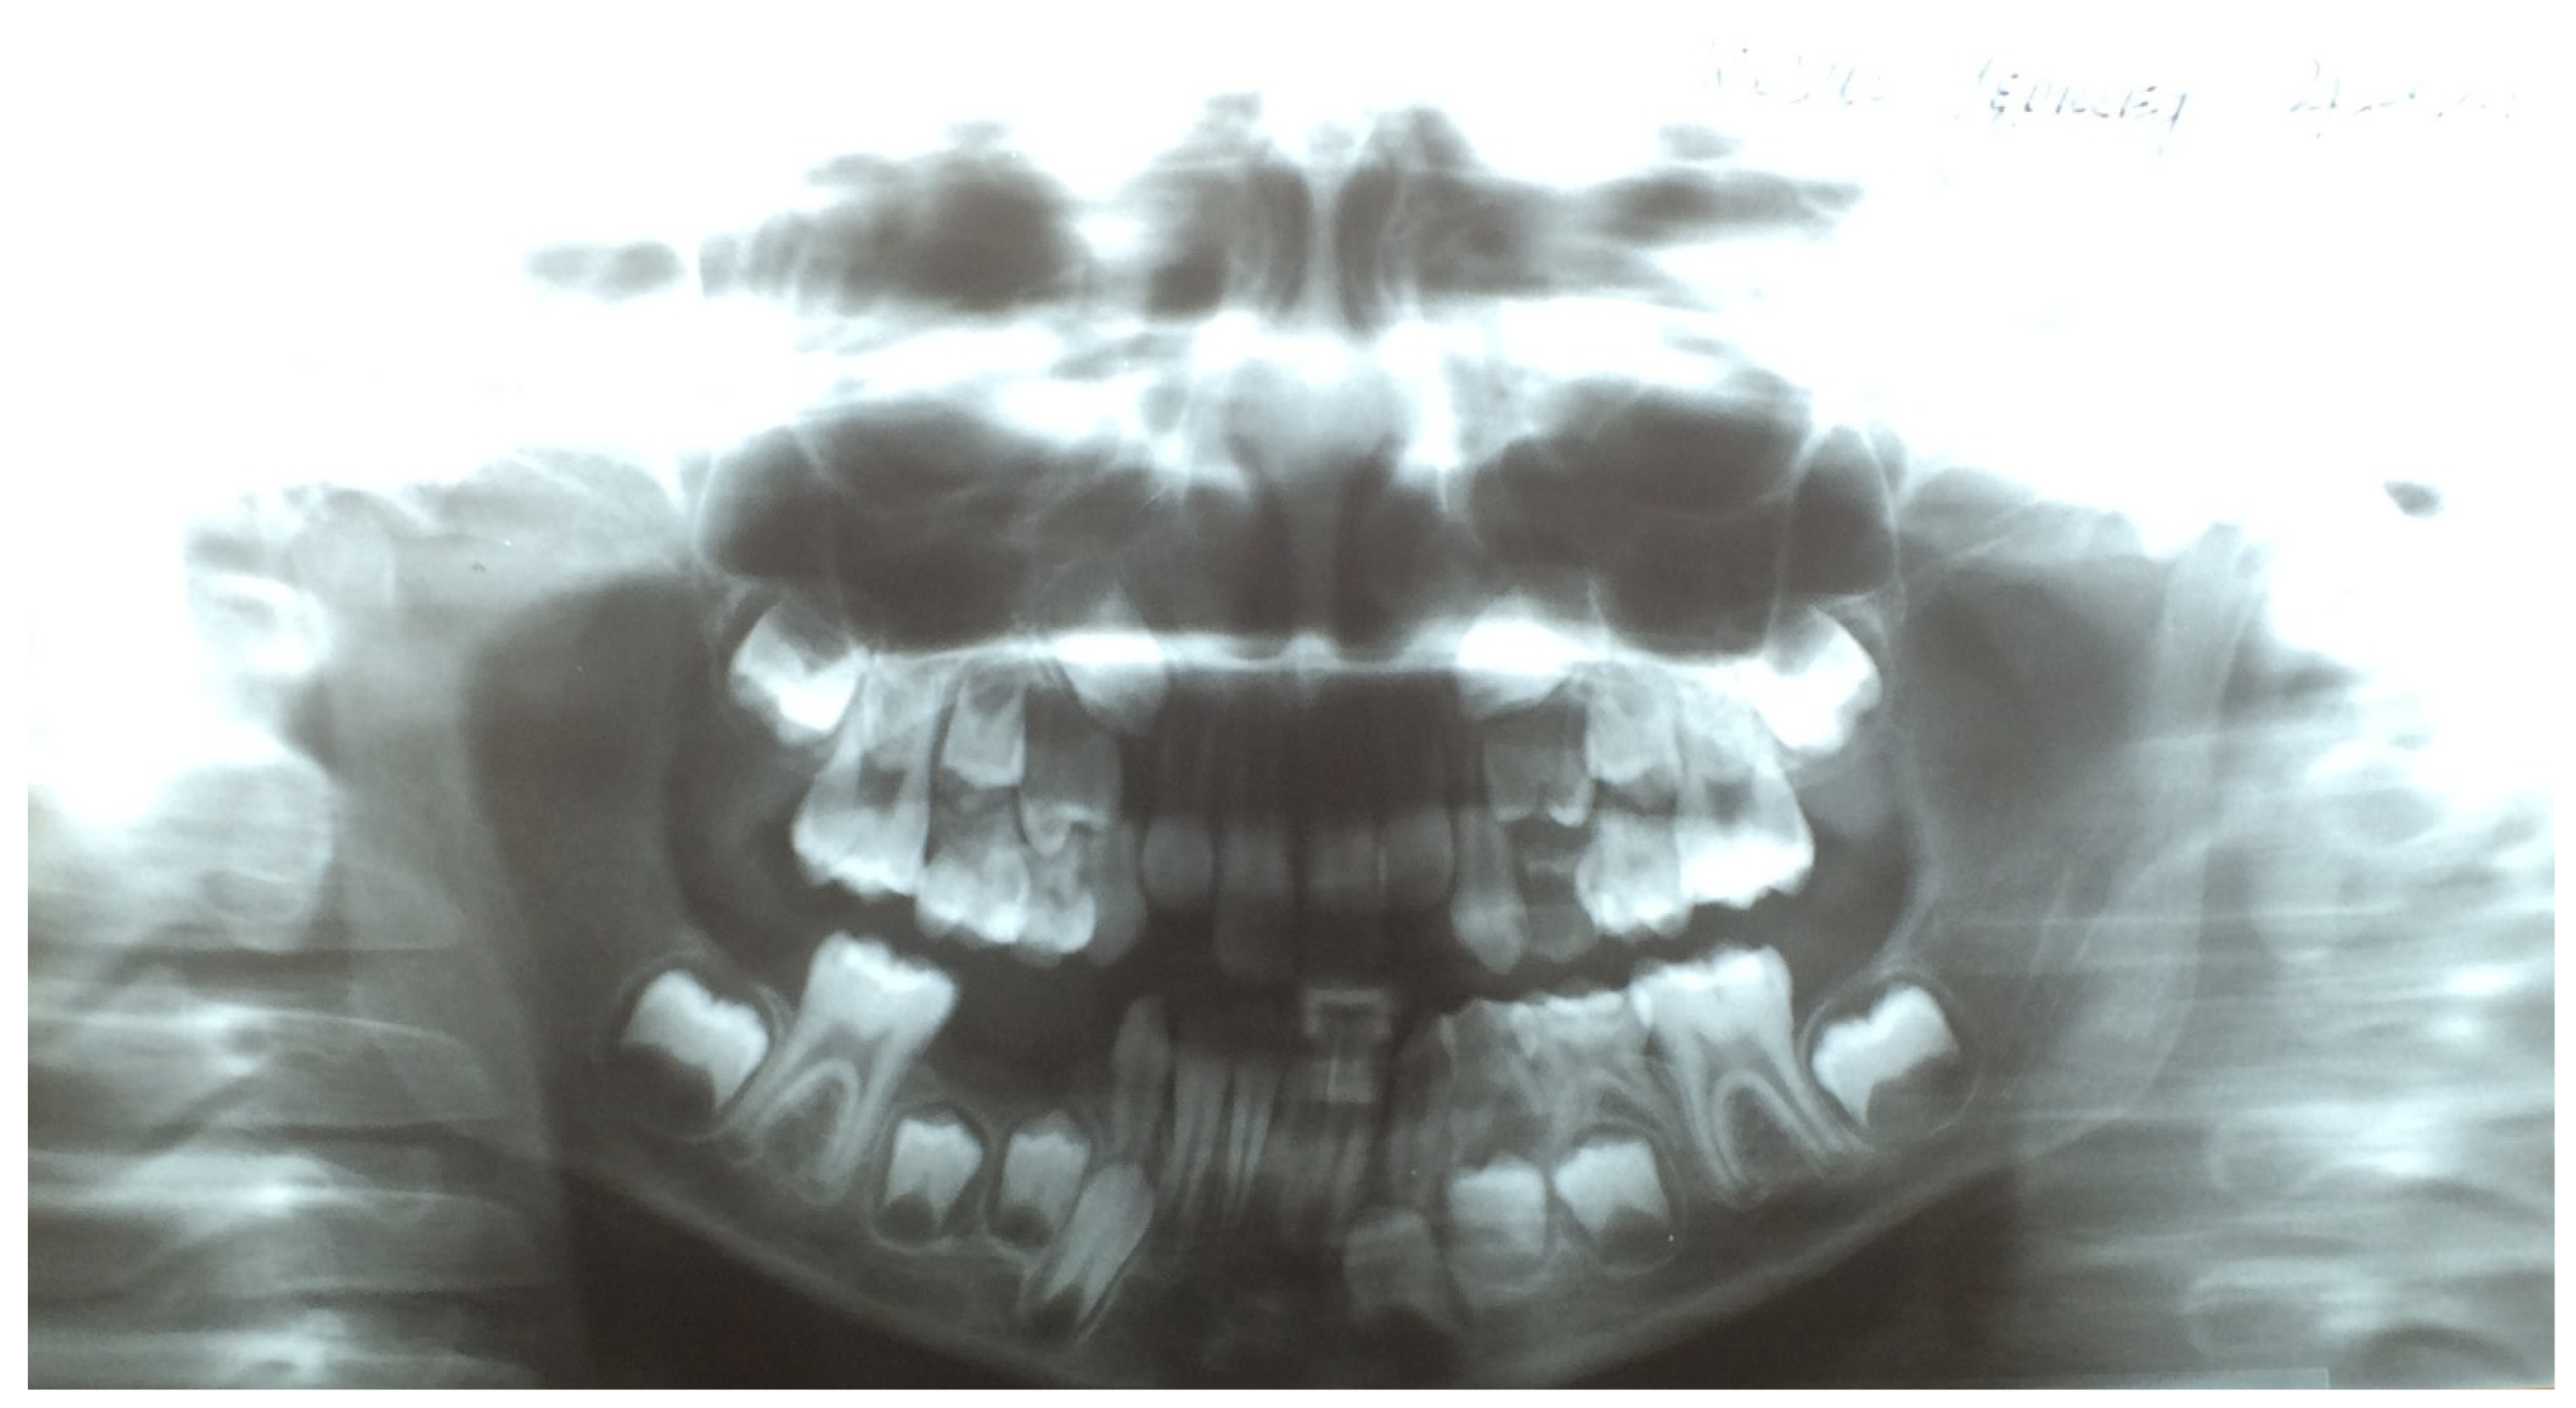

As mentioned above, in the case of upper teeth eruption, a discharge was present on the posterior wall of the throat. This caused a pharyngeal cough in about 88–89% of the investigated children. Coughing occurred mainly during the day and was a major concern for the parents. A pantomographic examination showed normal dentition, typical for the child’s age. There were no periapical changes, cysts, or bone inflammation. The X-ray procedure was not the cause of the aforementioned disease symptoms (Figure 1).

Figure 1.

Pantomographic radiograph of an 8-year-old girl.

In the course of teething, the tenderness and soreness of the mucosa cause infants to put their fingers and other objects in their mouth, stimulating saliva secretion. We observed that in older children, tooth eruption was accompanied by biting, gnawing, touching a sore spot with the tongue, or earache. Depending on whether the tooth emerged from the alveolar process of the mandibular or the jawbone, other symptoms also appeared. The most common were a cough and a runny nose, which are chronic in nature. They began in the moment the mucosa was pierced by the crown of a permanent tooth and increased in intensity until half of the crown had erupted. These symptoms gradually disappeared in the later stages of the tooth eruption. We observed clear differences in the type of cough associated with tooth eruption, depending on the type of teeth, the upper teeth being accompanied by pharyngeal cough, and the lower teeth by bronchial cough. Laboratory tests performed in the children during this period, such as complete blood count and C-reactive protein level, were normal. As for diagnostic imaging, sinus X-rays showed a slight thickening of the mucosa, while lung X-rays showed no focal lesions. Pharyngeal cough occurred mainly during the day and was a major concern for the parents. Combined with a runny nose, it led to a suspicion of chronic sinusitis. In this period, X-ray examination of the paranasal sinuses was performed in approximately 35% of the children, but apart from some local thickening of the mucosa, no pathological changes were revealed (Figure 1 and Figure 2). Nevertheless, approximately 25% of the children were referred for ENT consultations, and half of them were treated for chronic nonspecific sinusitis, often with antibiotics or nasal irrigation, with no significant improvement.